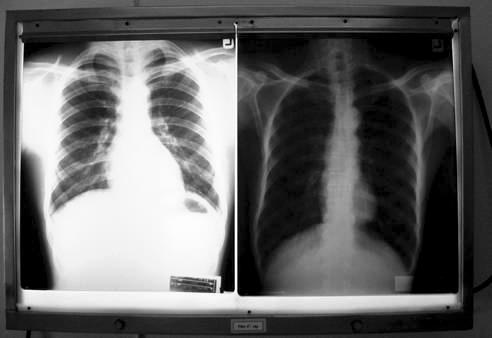

ผมใช้เวลากว่า 15 นาทีในการพยายามชักจูงให้ลุงอำนวยเลิกบุหรี่และเหล้า โดยผมส่งลุงอำนวยไปเอกซเรย์ปอด แล้วชี้ให้ดูว่าปอดของลุงยาวกว่าปอดปกติเท่าไหร่โดยใช้ไม้บรรทัดวัดเทียบกับเอกซเรย์ของคนปกติที่ผมเตรียมไว้ใช้เป็นประจำ.

การใช้ผลแล็บ เอกซเรย์ของตัวเขาเอง ที่นอกจากเพื่อการตรวจรักษาแล้ว ยังอาจจะได้ช่วยปรับเปลี่ยนพฤติกรรมคนไข้ ซึ่งจะส่งผลระยะยาวต่อสุขภาพของคนแต่ละคน.